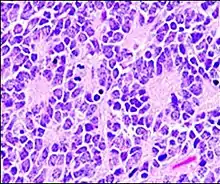

Homer Wright pseudorosette

A Homer Wright pseudorosette is a type of pseudorosette in which differentiated tumor cells surround the neuropil.[15] Examples of tumors containing these are neuroblastoma, medulloblastoma, pinealoblastoma, and primitive neuroectodermal tumors of bone. Homer Wright rosettes are considered "pseudo" in the sense that they are not true rosettes. True rosettes are Flexner–Wintersteiner rosette, which contain an empty lumen. Homer Wright rosettes contain abundant fibrillary material. They are named for James Homer Wright.

Structure of a Homer Wright pseudorosette